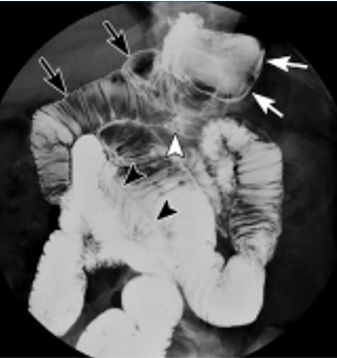

Menetrier’s disease

Classic appearance with massively enlarged folds in the body without abnormality in the antrum.

This condition is characterised by hypertrophy of gastric glands, achlorhydria and hypoproteinaemia. Loss of protein from the hyperplastic mucosa into the gastric lumen results in a protein-losing enteropathy, and may produce disabling symptoms. The disease is characterised by markedly enlarged, often bizarre gastric folds most prominent in the proximal stomach and along the greater curvature.